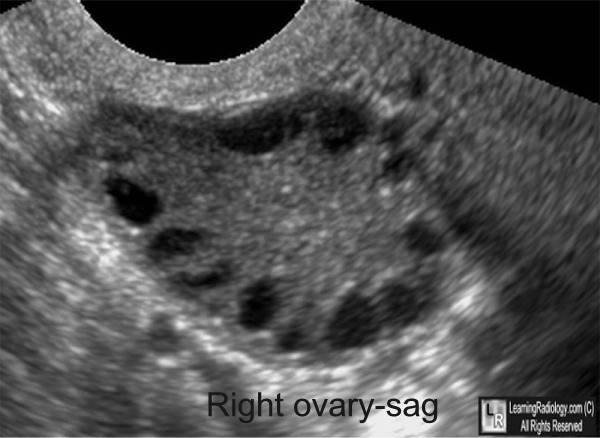

‘Pearl necklace’ ultrasound appearance of PCO (polycystic ovary)

-follicle develops but never ovulates